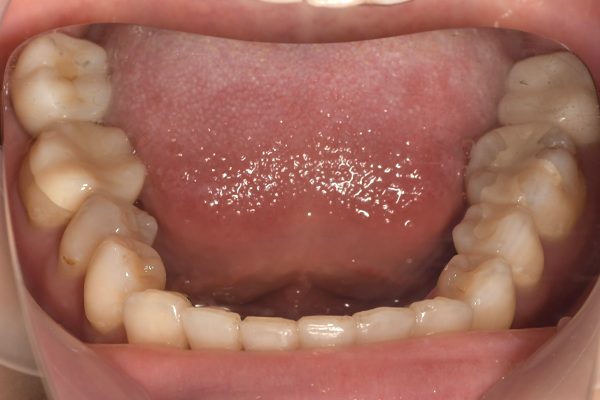

| 年齢・性別 | 20代・女性 |

|---|---|

| 主訴 | 左下5が欠けてしまい凍みる |

| 治療内容 | 左下Eの抜歯後インプラント埋入 |

| 治療費 | 【合計】572,000円 【内訳】ガイド 55,000円、静脈内鎮静法 77,000円、 インプラントハイブリッドクラウン 440,000円 |

| 治療期間 | 8ヶ月 |

| リスク・副作用 | 今後も虫歯や歯周病を進行させないように歯科衛生士による 歯みがき指導を受けていただく。 インプラント周囲炎 3ヶ月から6ヶ月の間に定期検診に 来ていただく。 噛んだ時に強すぎる力が加わるとインプラントの周りの骨に ダメージを与えてしまいひどい場合には骨の吸収が進み インプラントが脱落してしまう事がある。 夜間就寝時に装着するナイトガードを継続使用 していただく。 |

| 治療方針 | ブリッジ、入れ歯、インプラントについてご説明。 |

| 特記事項 | 費用面で問題がある患者様は『デンタルローン』をご選択いただく事が可能。 金利が安く歯科治療費に限定されたローン会社による立替払い制度。 費用が貯まるまで待たずに治療したい、毎月少しずつ無理なく 支払いたい患者様におすすめのお支払い方法。 |

| 担当者所見 | 左側のかみ合わせが低かったので、骨を削除してしっかり左右で 噛むことが出来るようにかみ合わせを作ってからインプラントを埋入した。 |